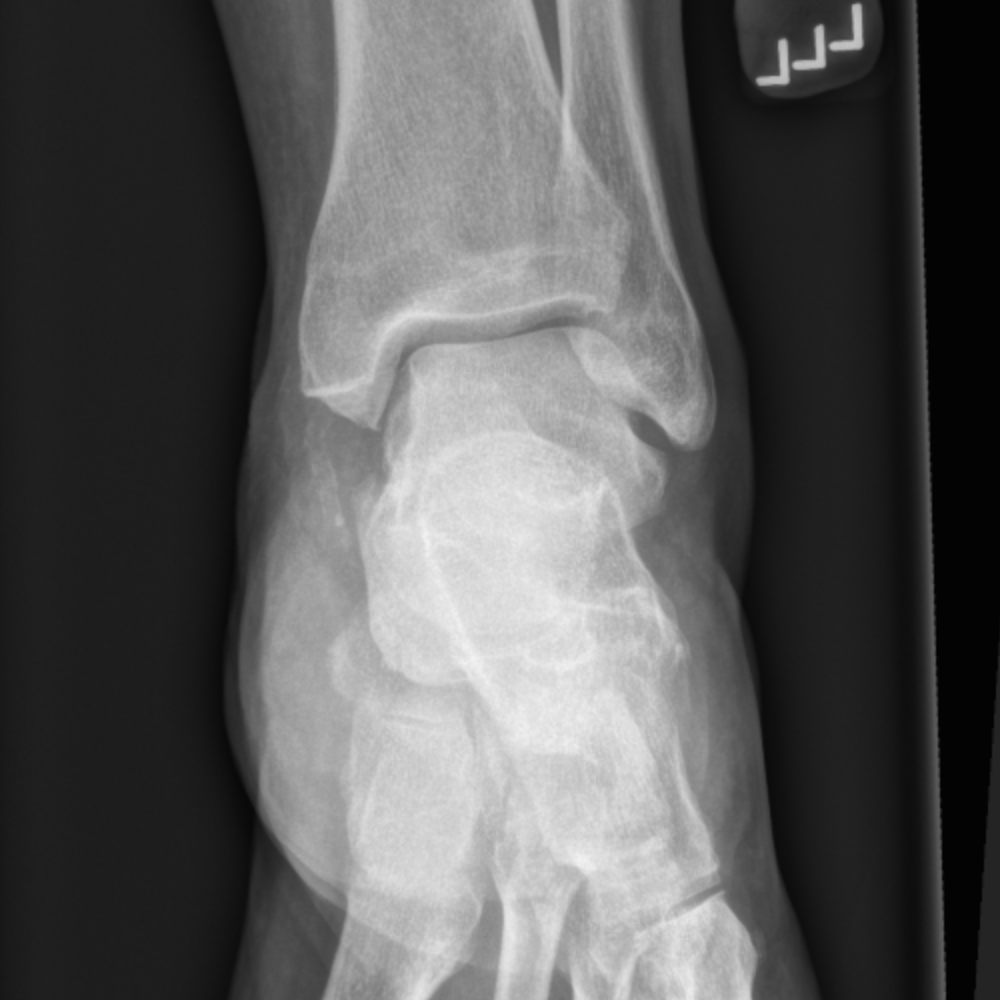

A calcaneal fracture is a break of the calcaneus (heel bone). Calcaneal fractures are often open and can be complicated by osteomyelitis, septic calcaneal bursitis, sequestration, and chronic drainage. It is a rare type of fracture but has potentially debilitating results.

A systematic evaluation of associated conditions. If a calcaneus injury is found, look for concomitant. Loading stack minimally displaced but slightly comminuted fracture of the anterior process calcaneus (arrows) with considerable overlying soft tissue swelling involving the subcutaneous tissues and bifurcate ligament. Comorbidities that preclude good surgical outcome (smoker, diabetes, pvd). • most intraarticular calcaneus fractures are the result of an axial load applied directly to the heel. Inversion with plantar flexion can lead to an avulsion fracture. A systematic evaluation of associated conditions. Fractures of the anterior process of the calcaneus occur following an acute injury to the foot. Symptoms may include pain, bruising, trouble walking, and deformity of the heel. J am podiatry assoc 1984;74(8): S92.021a displaced fracture anterior process right calcaneus, initial closed. Sclerotic line may be only evidence of impacted fracture. Answer | the anterior process of the calcaneus usually fractures due to an avulsion or traction injury. Calcaneal fractures are often open and can be complicated by osteomyelitis, septic calcaneal bursitis, sequestration, and chronic drainage. Anterior process fracture involving <25% of calcaneocuboid joint. Anterior process of calcaneus fracture. Fracture of anterior process of calcaneus.